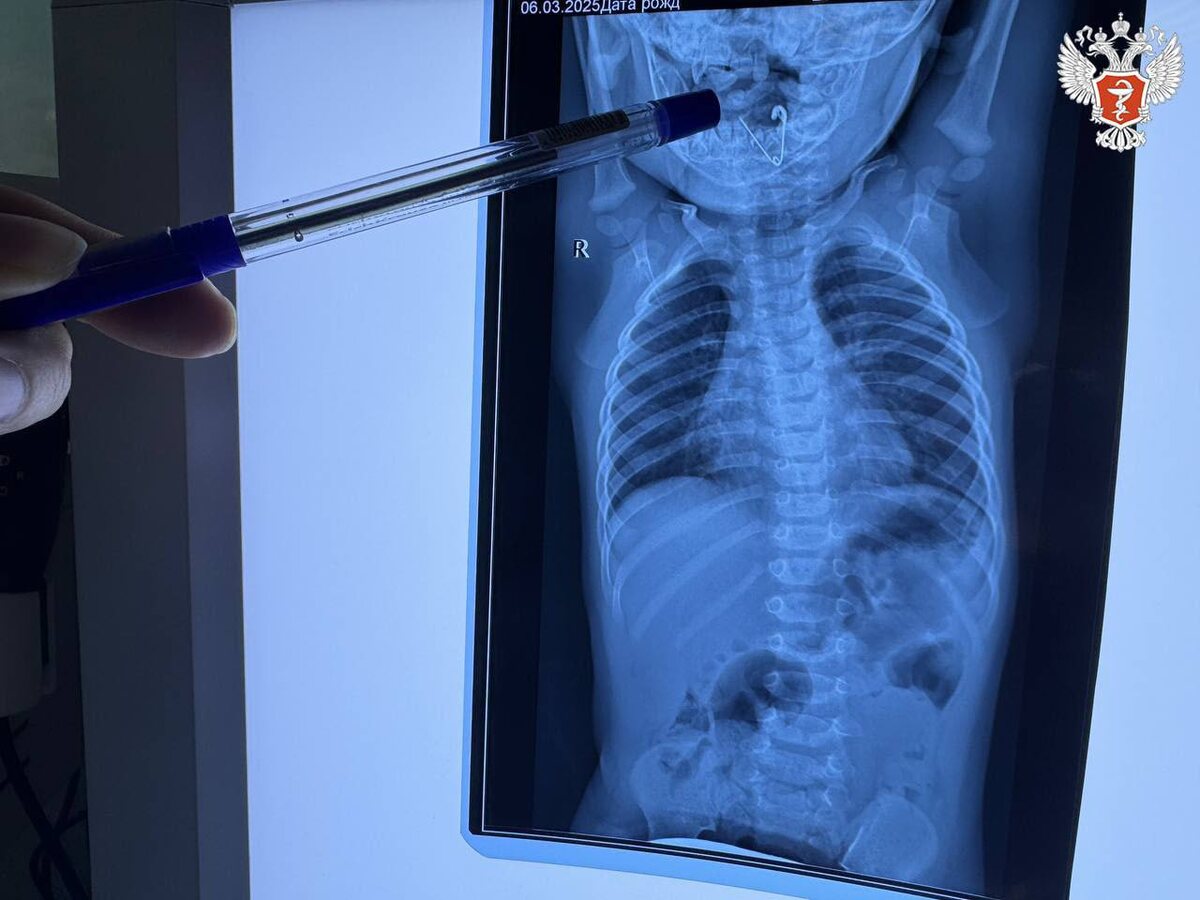

Бригада медиков госпитализировала маленького пациента в приемное отделение Черниговской центральной районной больницы. Специалисты выполнили обзорную рентгенографию органов грудной клетки и в пищеводе обнаружили тень инородного тела.

Малышу провели повторное рентгеновское исследование и на снимке увидели открытую булавку. Врачи удалили ее при помощи щипцов под контролем эндоскопической техники. Операцию по извлечению инородного тела провели заведующая ЛОР-отделением первой детской больницы Светлана Таранова и ее коллега – заведующий эндоскопическим отделением Алексей Ткачук.